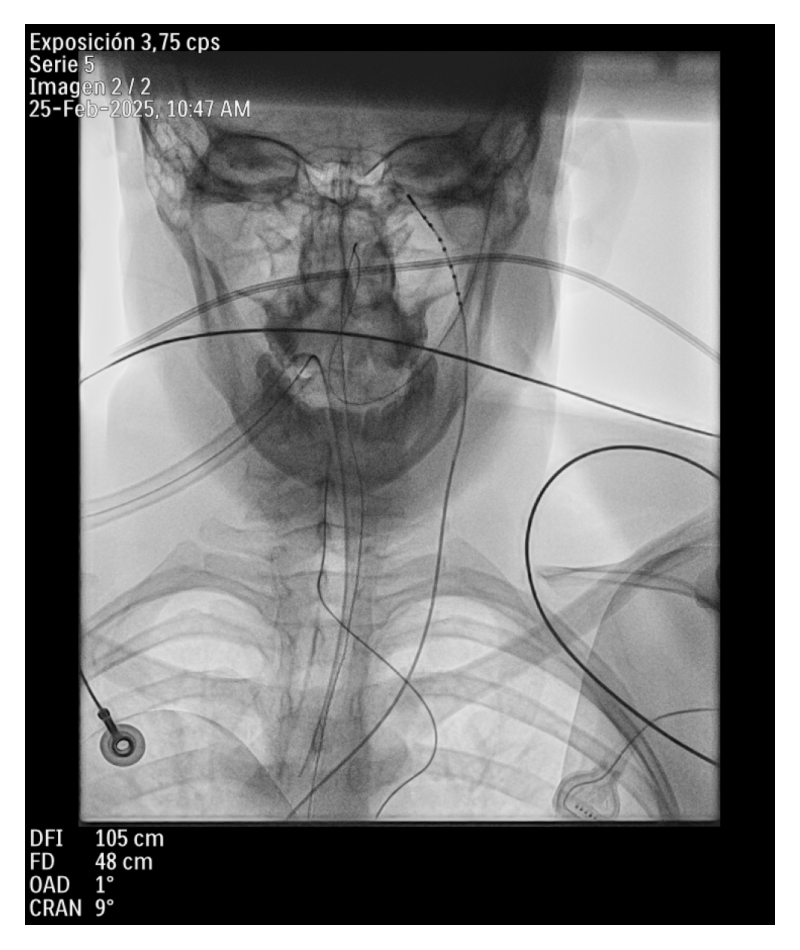

Varón de 19 años con antecedentes de trastorno por déficit de atención e hiperactividad (TDAH) y SNM recurrente. El holter implantable registró pausas de hasta 8 segundos secundarias a bloqueo auriculoventricular completo, motivo por el que se CNA. Bajo anestesia general, se observa respuesta parasimpática exagerada. Se aplica posteriormente RF sobre el ganglio posteroseptal y la vena pulmonar inferior derecha, logrando supresión de respuesta vagal y aumento de la frecuencia sinusal.